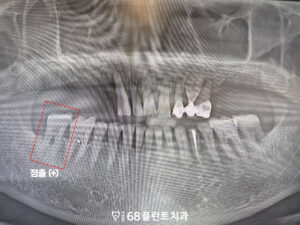

또한 오른쪽 아래 맨 뒤 치아는

맞닿는 위 치아가 없어

점점 정출되어 올라온 상태였습니다.

대합치가 없는 상태가 오래 지속되면서

해당 치아가 위로 자라 나오듯 이동하였고,

그로 인해 교합 평면이 흐트러진

모습이 확인되었습니다.

그리고 해당 치아 역시

치주염의 영향으로

치근분지부까지 골 소실이

진행된 상태였습니다.

그래서 발치 후 철산역임플란트를

함께 식립하기로 계획을 수립하였습니다.

마지막으로 왼쪽 아래 치아는

오래 전 신경치료를 받은 이후,

위 보철을 씌우지 않고

치료를 중단한 상태였으며

그로 인해 치관부가

파절된 모습이 확인되었습니다.

신경치료를 받은 치아는 내부 수분이 감소해

상대적으로 취약해질 수 있는데,

보철 수복 없이 장기간 사용하게 되면

저작 압력에 의해 균열이나

파절이 발생할 가능성이 높습니다.

그래서 해당 치아도

발치 후 임플란트를 식립하기로 하였으며

전체적인 치료 계획을 전부 수립하였습니다.